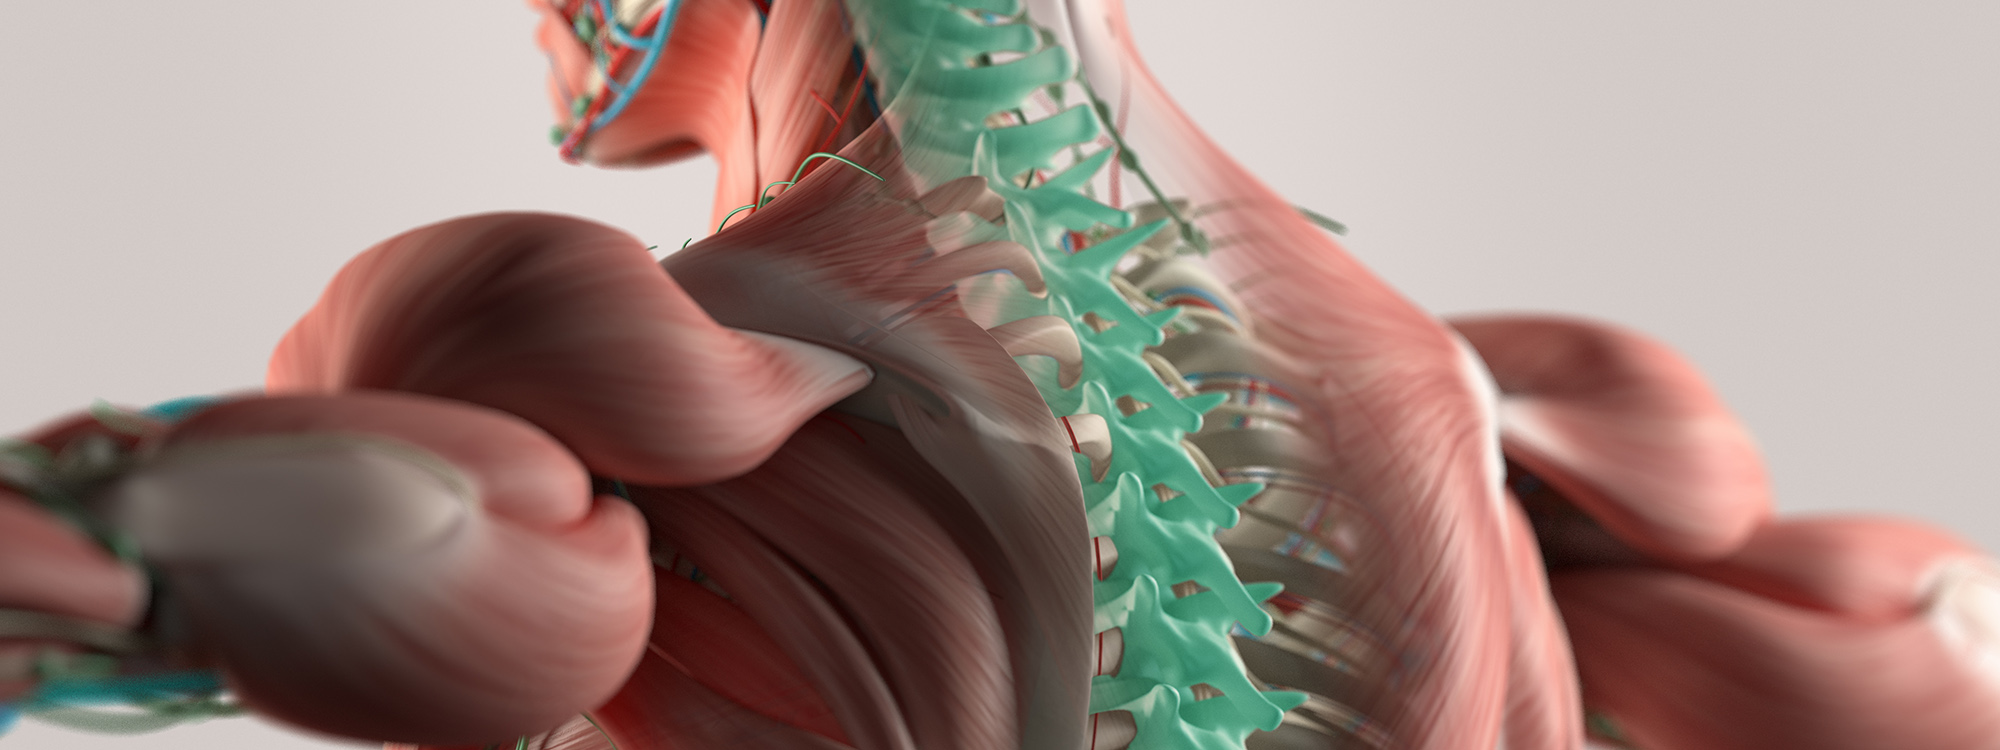

OUR DOCTORS ARE HERE FOR YOU! – THESE & OTHER SERVICES AVAIALBLE:

Reasons why Regional Spine & Pain is your BEST Choice!

Conditions We Treat

When you visit us for chiropractic care and therapy, our staff will be focused on properly diagnosing you to determine the best care plan going forward, but more importantly, we will focus on you as a human being. We are not just treating back pain - we are treating you holistically. Your situation is unique to your circumstances, and we factor that in.